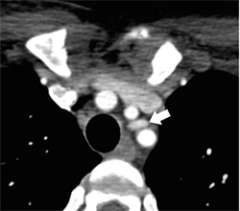

Figure 2. Parathyroid 4D-CT showing a parathyroid adenoma in an abnormal position within the mediastinum.

Figure 3. Parathyroid 4D-CT showing a parathyroid adenoma in an abnormal position within the mediastinum.